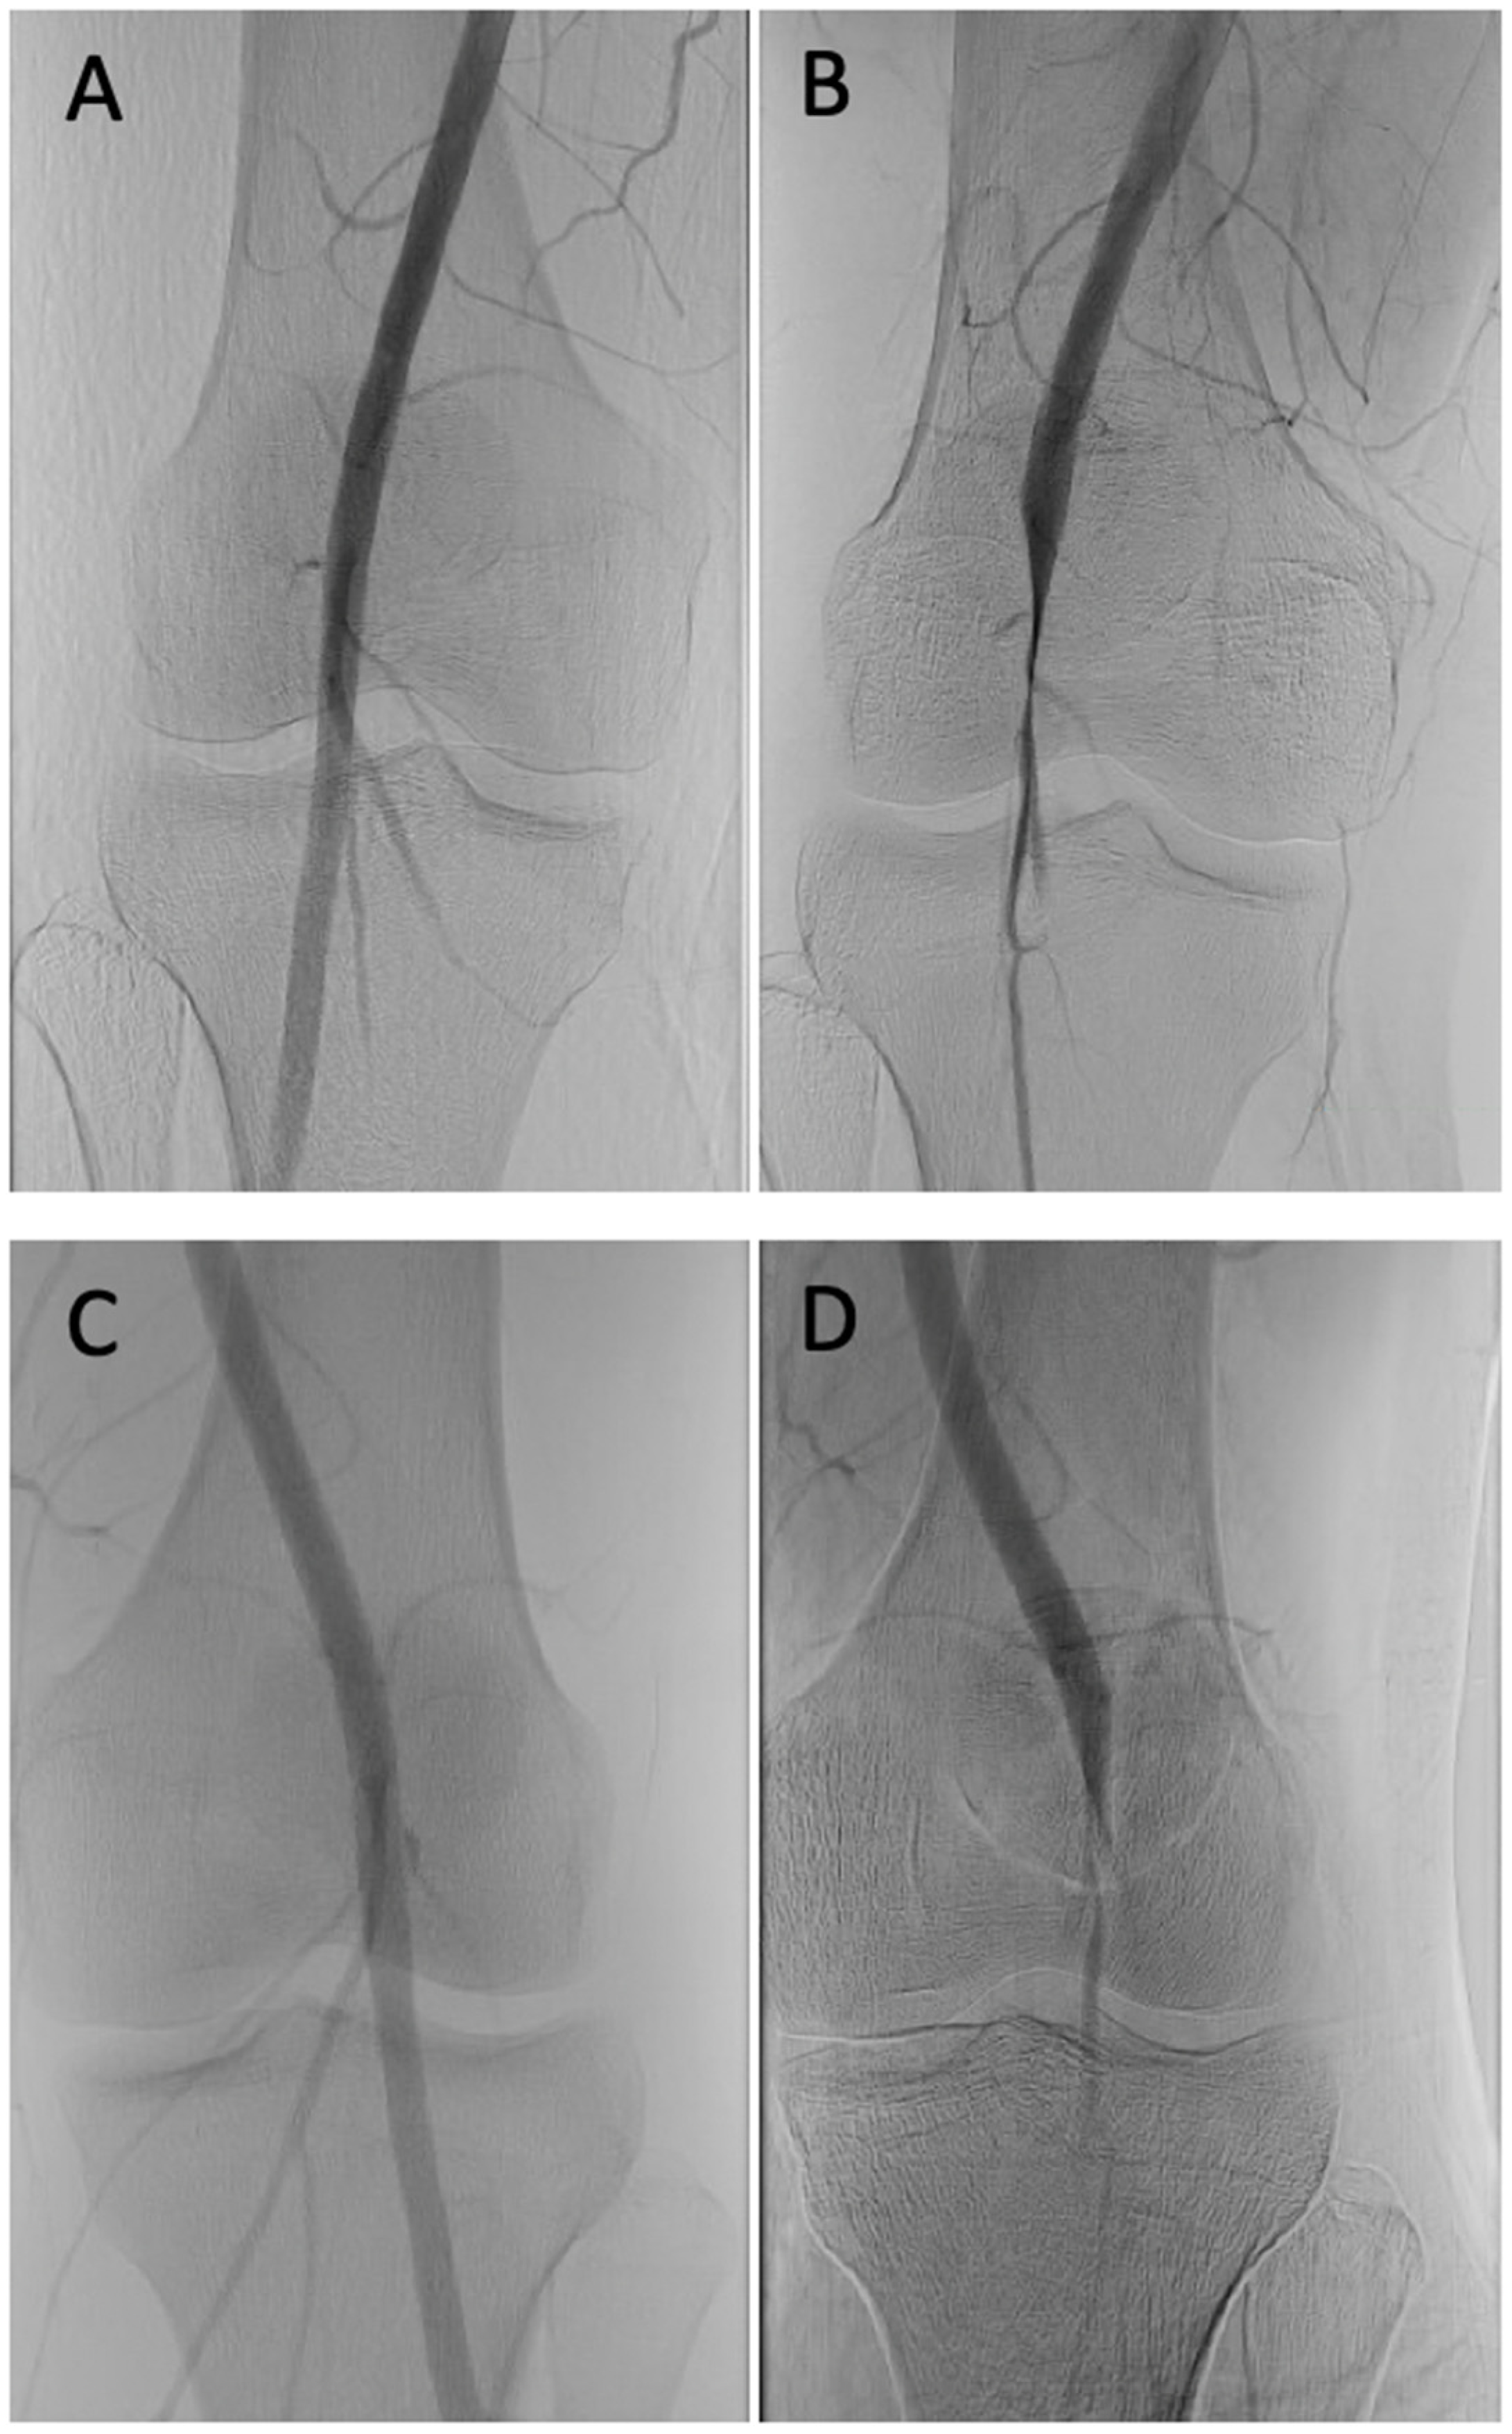

2.2. Diagnostic Testing

2.3. Definitive Treatment

3.5. Modalities of Imaging